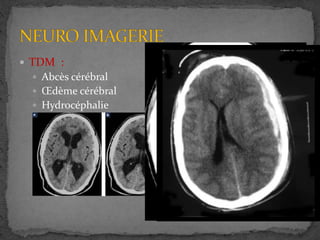

 NEURO IMAGERIE

 TDM :

 Abcès cérébral

 Œdème cérébral

 Hydrocéphalie

 Hématome sous durale